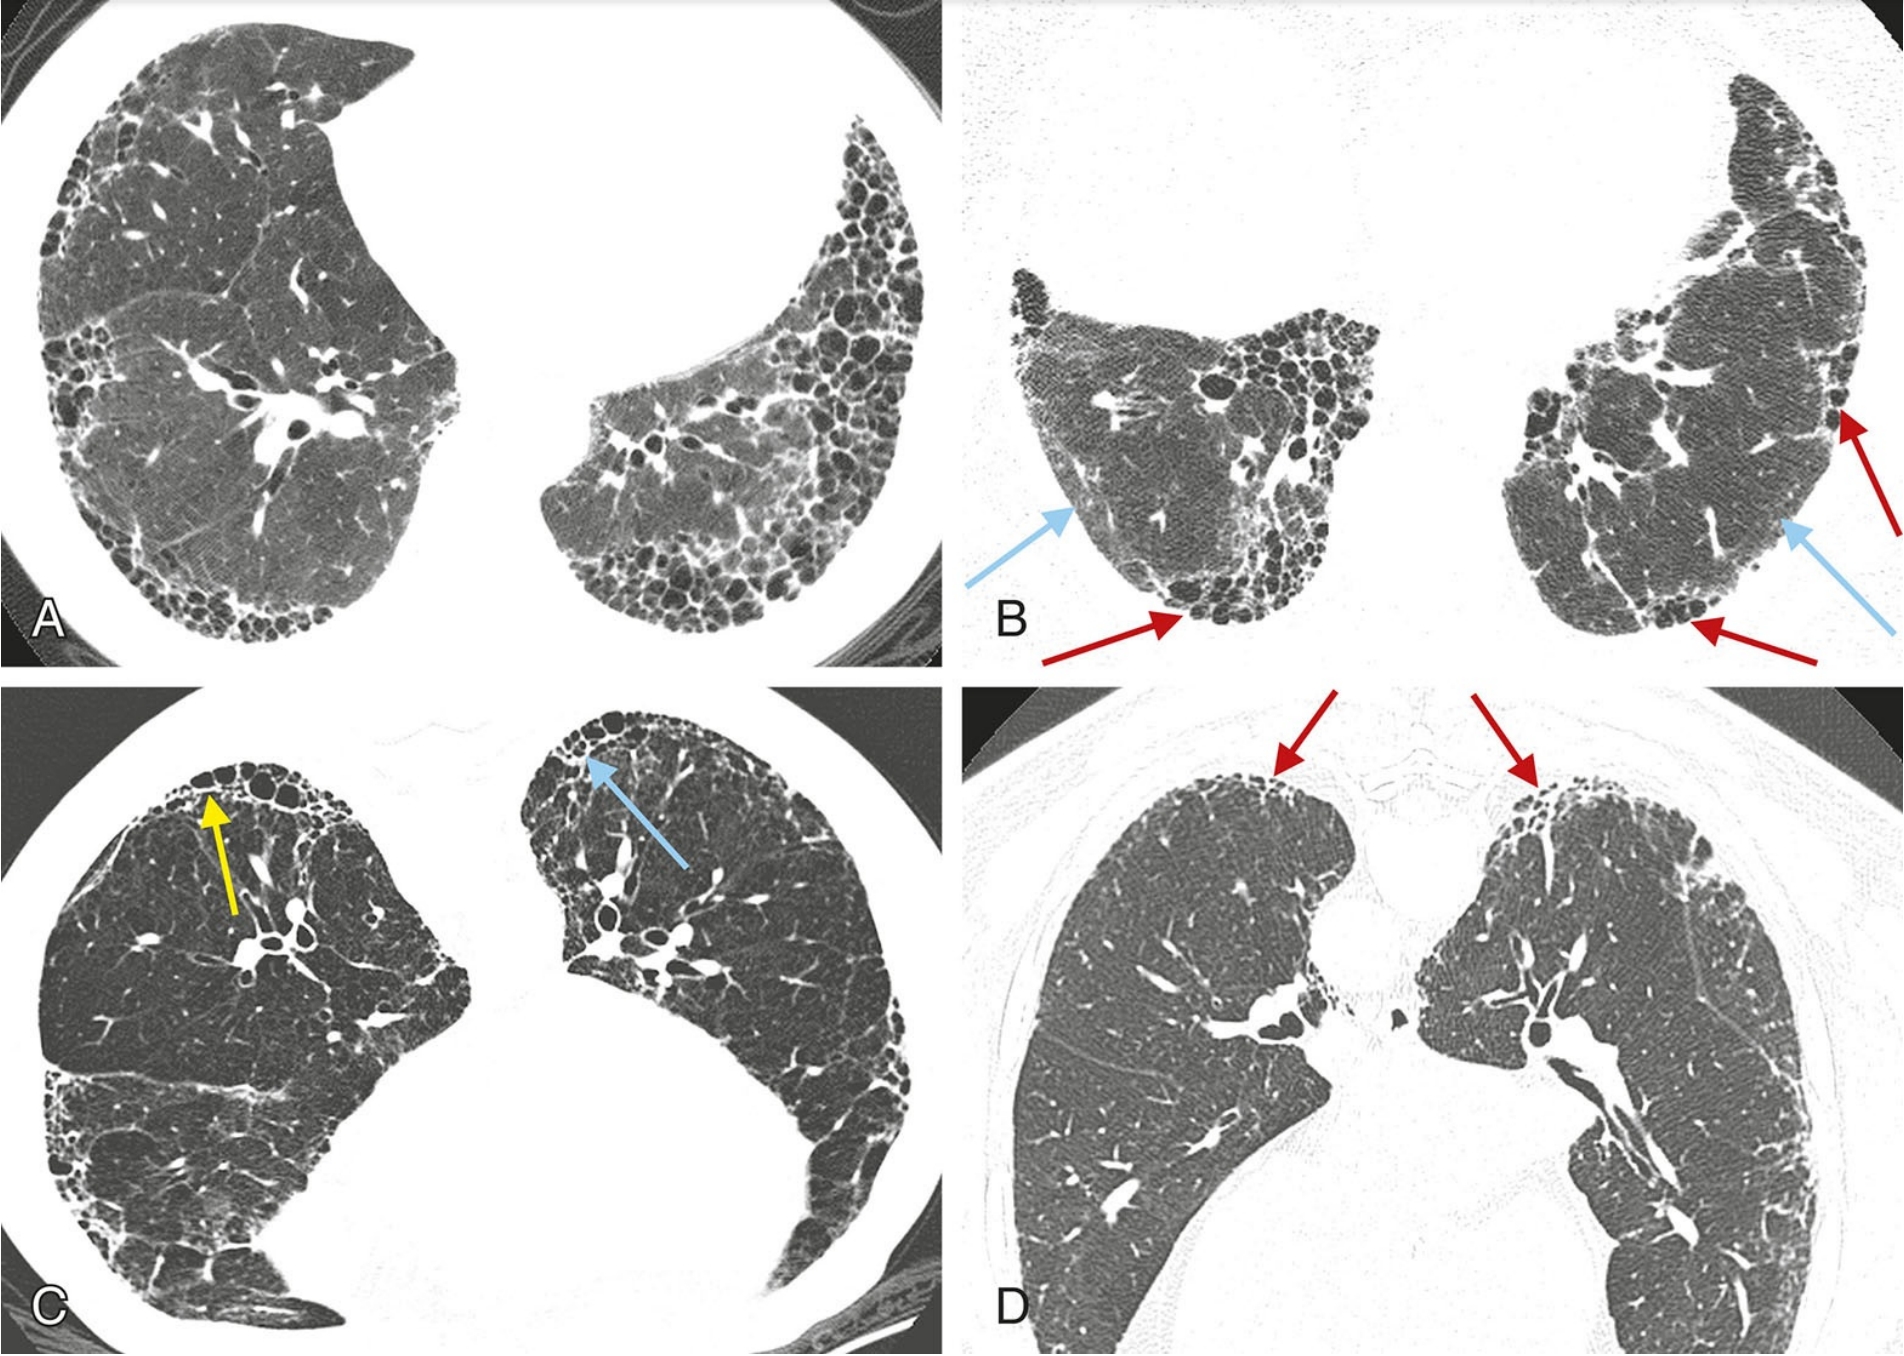

ffd7bb23e755e95335b0c12dc29c866a.png

普通型间质性肺炎(UIP)的典型表现。

A.伴有特发性肺纤维化的UIP模式患者,HRCT显示广泛的胸膜下和肺基底分布为主的蜂窝征;

B.散在分布的胸膜下蜂窝征(红箭),与相对正常的肺组织(蓝箭)相间;

C.俯卧位HRCT显示UIP患者的蜂窝征(箭),可为单层(黄箭)或多层(蓝箭);

D.早期UIP表现为轻度的胸膜下网状影和蜂窝征,虽然程度轻微,但仍可明确判定蜂窝征(箭)。